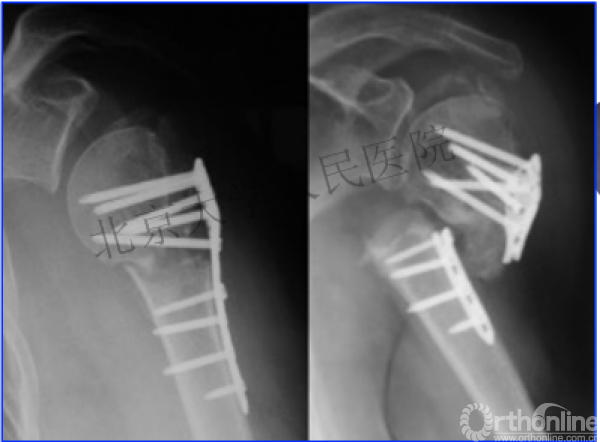

另一个留有遗憾的病例,您的选择?PHN?

临床中的广泛内固定治疗不断地提出思考

结构力学上抗折断能力髓内钉明显强于钢板

三、其实应用肱骨近端髓内钉治疗肱骨近端骨折有时有许多优势。

两部分骨折的生物力学

作为髓内固定,抗轴向压力较偏心固定的钢板强。